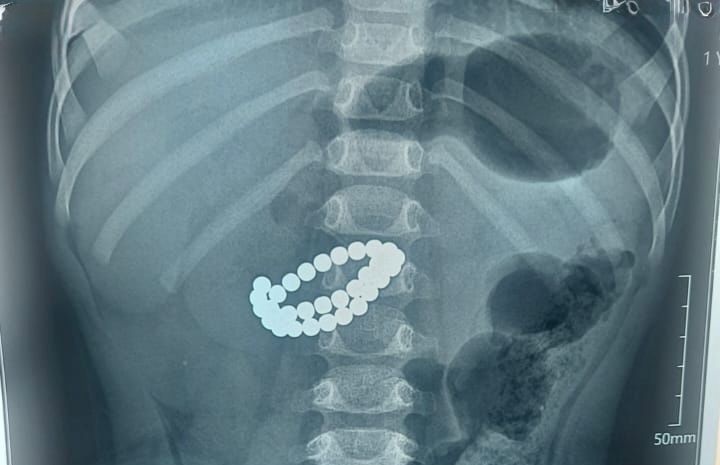

В приемное отделение в крайне тяжелом состоянии поступил малыш в возрасте 1 года 9 месяцев. После обследования врачи установили диагноз: инородные тела кишечника – 31 магнит, множественные перфорации тонкой кишки, диффузный каловый перитонит.

Единственным шансом спасти жизнь ребенка стало срочное хирургическое вмешательство. Медики выполнили срединную лапаротомию с ревизией органов брюшной полости. Хирурги извлекли магниты из кишечника, ушили множественные перфорации тонкой кишки, провели санацию и дренирование брюшной полости, а также трансанальную интубацию кишечника.